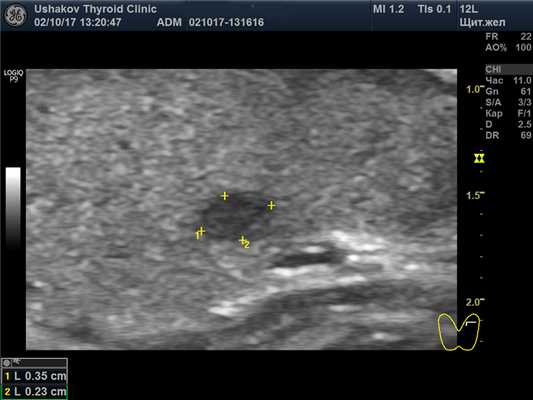

В левой доле щитовидной железы преобладает почти однородная изоэхогенная ткань, среди которой заметны два малых узла. В краниальном полюсе овоидоподобый узел 4,2х2,7х2,8 мм с чёткой границей, неоднородный: умеренно гипоэхогенный (за счёт деструкции), с малым изоэхогенным участком ткани; при ЭДК заметен крупный сосуд у края узла; при эластографии SR 2,5. Подобной организации, но более гипоэхогенный (тканевой) узел расположен в каудально-дорсальной части левой доли 2,5х2,3х4,3 мм; при эластографии SR 3,1. В режиме ЦДК и ЭДК кровообращение оптимальное.

Рис. 27.2. Пример 1. (левая доля, продольная проекция, краниальный полюс; ЭДК).

В кранио-вентральной части узла преобладает деструкция; видна анэхогенная (жидкостная) прикраевая зона. Дорсально – остаточная изоэхогенная ткань. У края узла расширенный сосуд с разветвлением сети.

Рис. 27.3. Пример 1. (левая доля, продольная проекция, каудально-дорсальная область). Чёткая граница долькового узла, в котором заметны мелкие точечные умеренно гипоэхогенные включения (признак деструкции).

Рис. 27.4. Пример 1. (левая доля, продольная проекция; ЭДК).

Количество сосудистых элементов указывает на оптимальный уровень кровотока, пограничный с малым усилением.

Узловые образования левой доли можно отнести к дольковому процессу. Это малые, т.е. долькового происхождения, узлы. Поэтому их периметр из капиллярной сети имеет характерную для дольковых узлов тонкую, несколько «ломаную», малозаметную (даже местами незаметную) гипоэхогенную кривую линию-контур (рис. 27.3).

Рядом с такими узлами при ЭДК обычно можно заметить один или несколько сосудистых элементов (рис. 27.2. и 27.4). Приносимая с нервными ветвями (они сопровождают сосуды) к этим долькам нервная импульсация суммационно вызывает избыточное обособленное перенапряжение этого долькового сегмента, в котором также происходят последовательные стадийные преобразования (избыточная пролиферация на стадии развития и увеличение деструкции на стадии истощения).